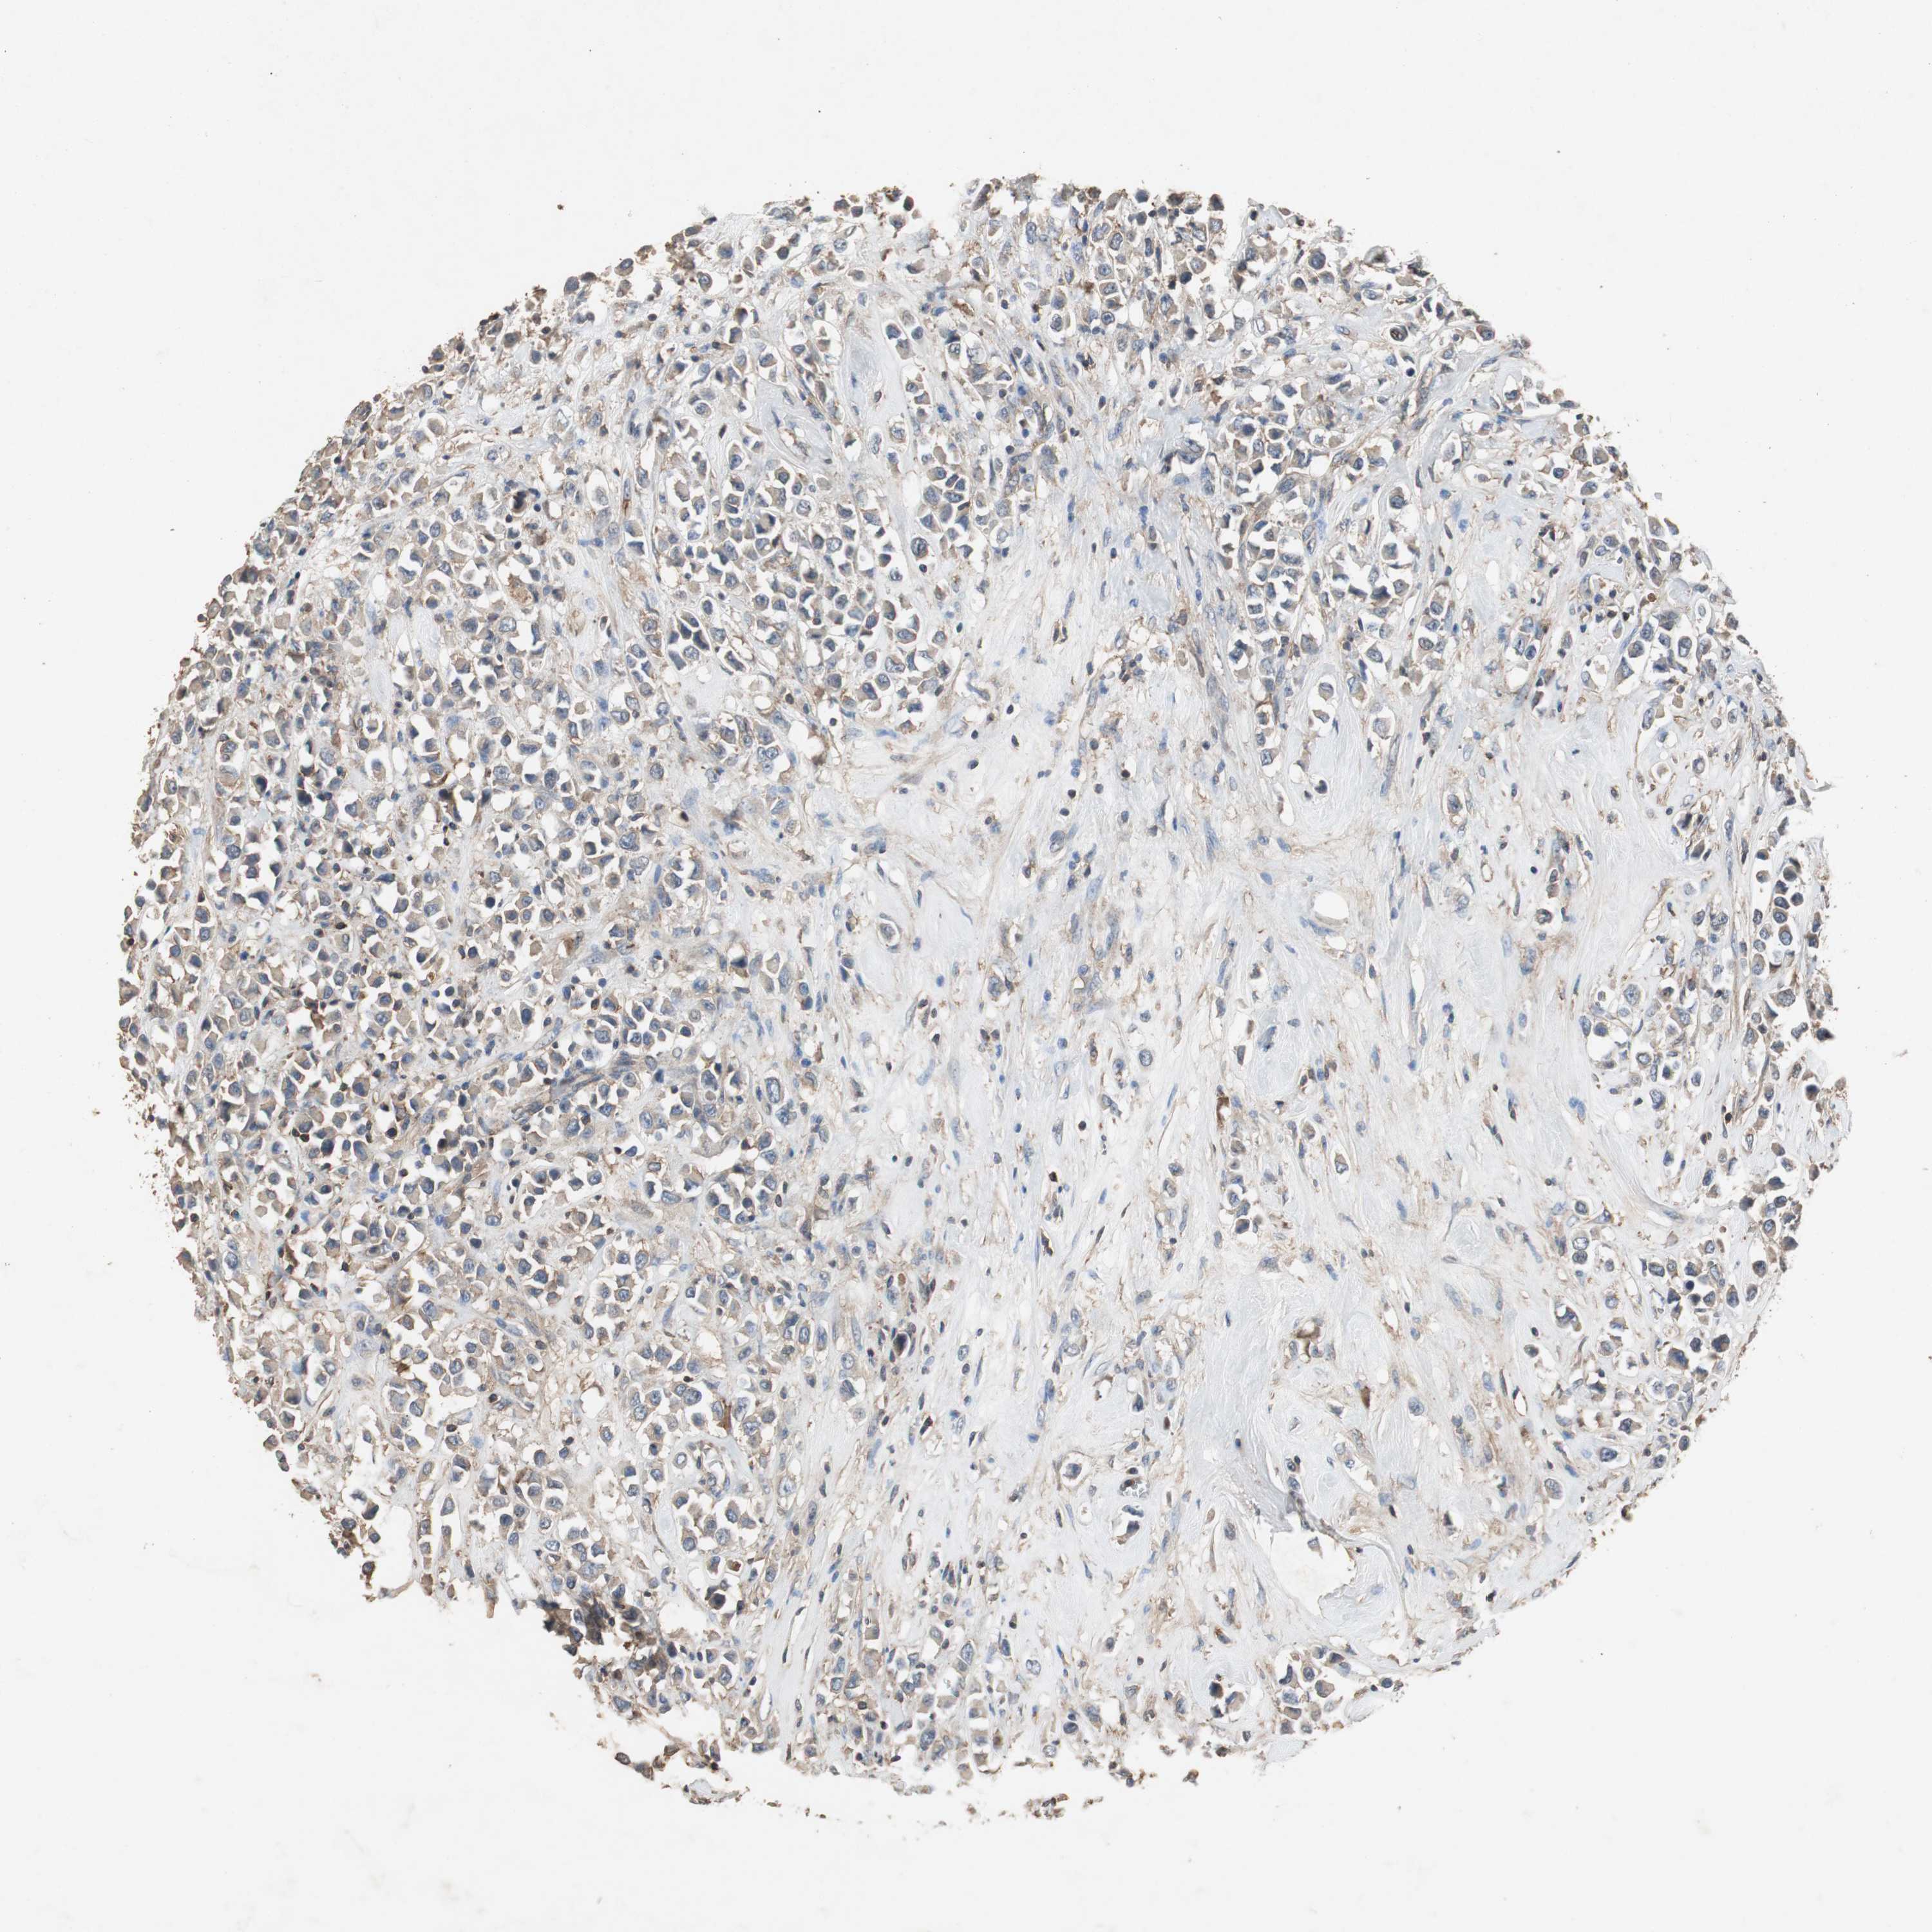

CANCER BREAST CANCER Show tissue menu

BRCA TCGA BRCA VALIDATION PROTEIN EXPRESSION